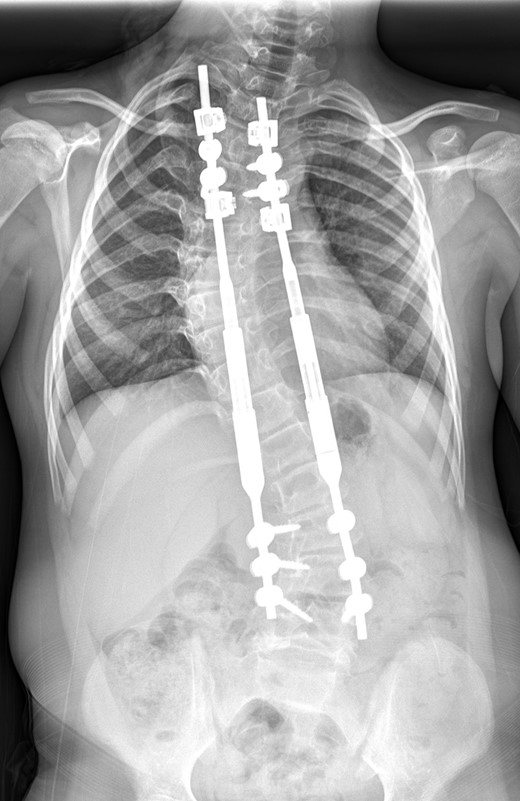

Between the ages of 4 and 6 years, the curve increased rapidly leading to a significant curve measuring 80° in the thoracic spine and 65° in the thoracolumbar spine with a T1–S1 height of 232 mm and T1–T12 height of 150 mm (Fig. 1). A decision was made to intervene operatively and posterior instrumentation with MCGR was performed. Special consideration was given to her bone fragility. Following 4.5 years of bisphosphonate therapy, her last bone mineral density (BMD) assessment by dual energy X-ray absorptiometry before surgery was normal. Her lumbar spine BMD Z-score was +1.5 and the total body less head BMD Z-score was also +1.5. Thus, at age 6 years, a construct of three paired sets of pedicle screws were placed at L2–L4 distally and a combination of pedicle screws at two levels (T4 and T5), with an outer square of sublaminar bands passed under the third and sixth ribs, was placed proximally. The instrumentation used was a 4.5 Expedium System (DePuy Synthes, Raynham, MA, USA) and the Silc Sublaminar Banding System (Globus Medical, Audubon, PA, USA). Post-operative radiographs (Fig. 2) showed good spinal balance and correction of deformity, but fractures of the right 5th and 10th ribs were seen posteriorly at the junction of the rib and transverse process. Following 8 weeks of spinal cast jacket protection, a CT scan showed the rib fractures to have healed. After instrumentation the thoracic curve angle measured 38° and the thoracolumbar curve measured 30°, with a T1–S1 height of 247 mm and a T1–T12 height of 160 mm.

An immediate post-operative whole spine radiograph demonstrating the spinal construct with the MCGR rods (measuring 38° in the thoracic curve and 30° the thoracolumbar curve with a T1–S1 height of 247 mm and a T1–T12 height of 160 mm).